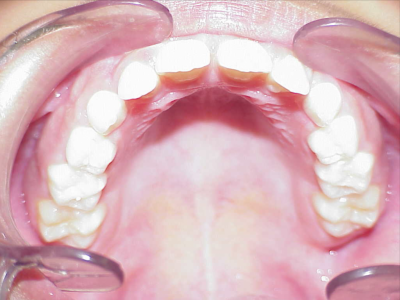

eindfoto

1-6 maanden Bonded Hyrax in de bovenkaak, banden/slotjes in de onderkaak met Transforce